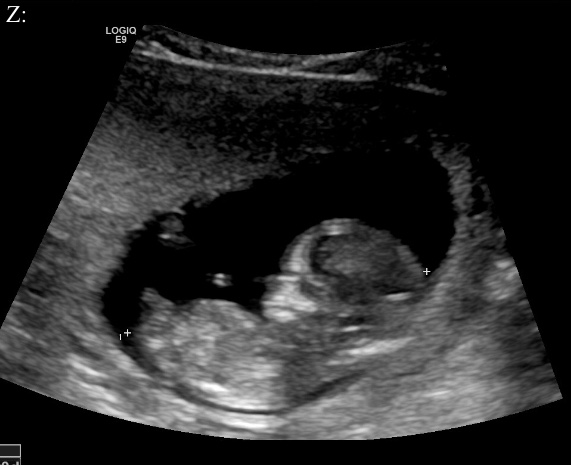

Hi guys. I’m posting 2 profile photos and 2 potty shots from my 12 week scan (measure 12w1d). I am not sure if either of the profile photos show a nub - if so, what are your guesses based on either of the profile photos or the potty shot?

I see 3 lines in the potty shot but the middle line is much longer pointing out. I will update on Friday when I find out but would love some guesses until then. TIA. Attachment 39791Attachment 39792Attachment 39793Attachment 39794